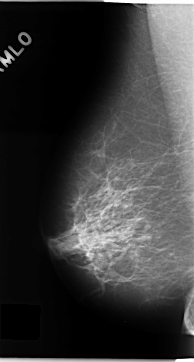

C_0133_1.LEFT_MLO

RIGHT_MLO LINES 4704 PIXELS_PER_LINE 2520 BITS_PER_PIXEL 12 RESOLUTION 50 NON_OVERLAY